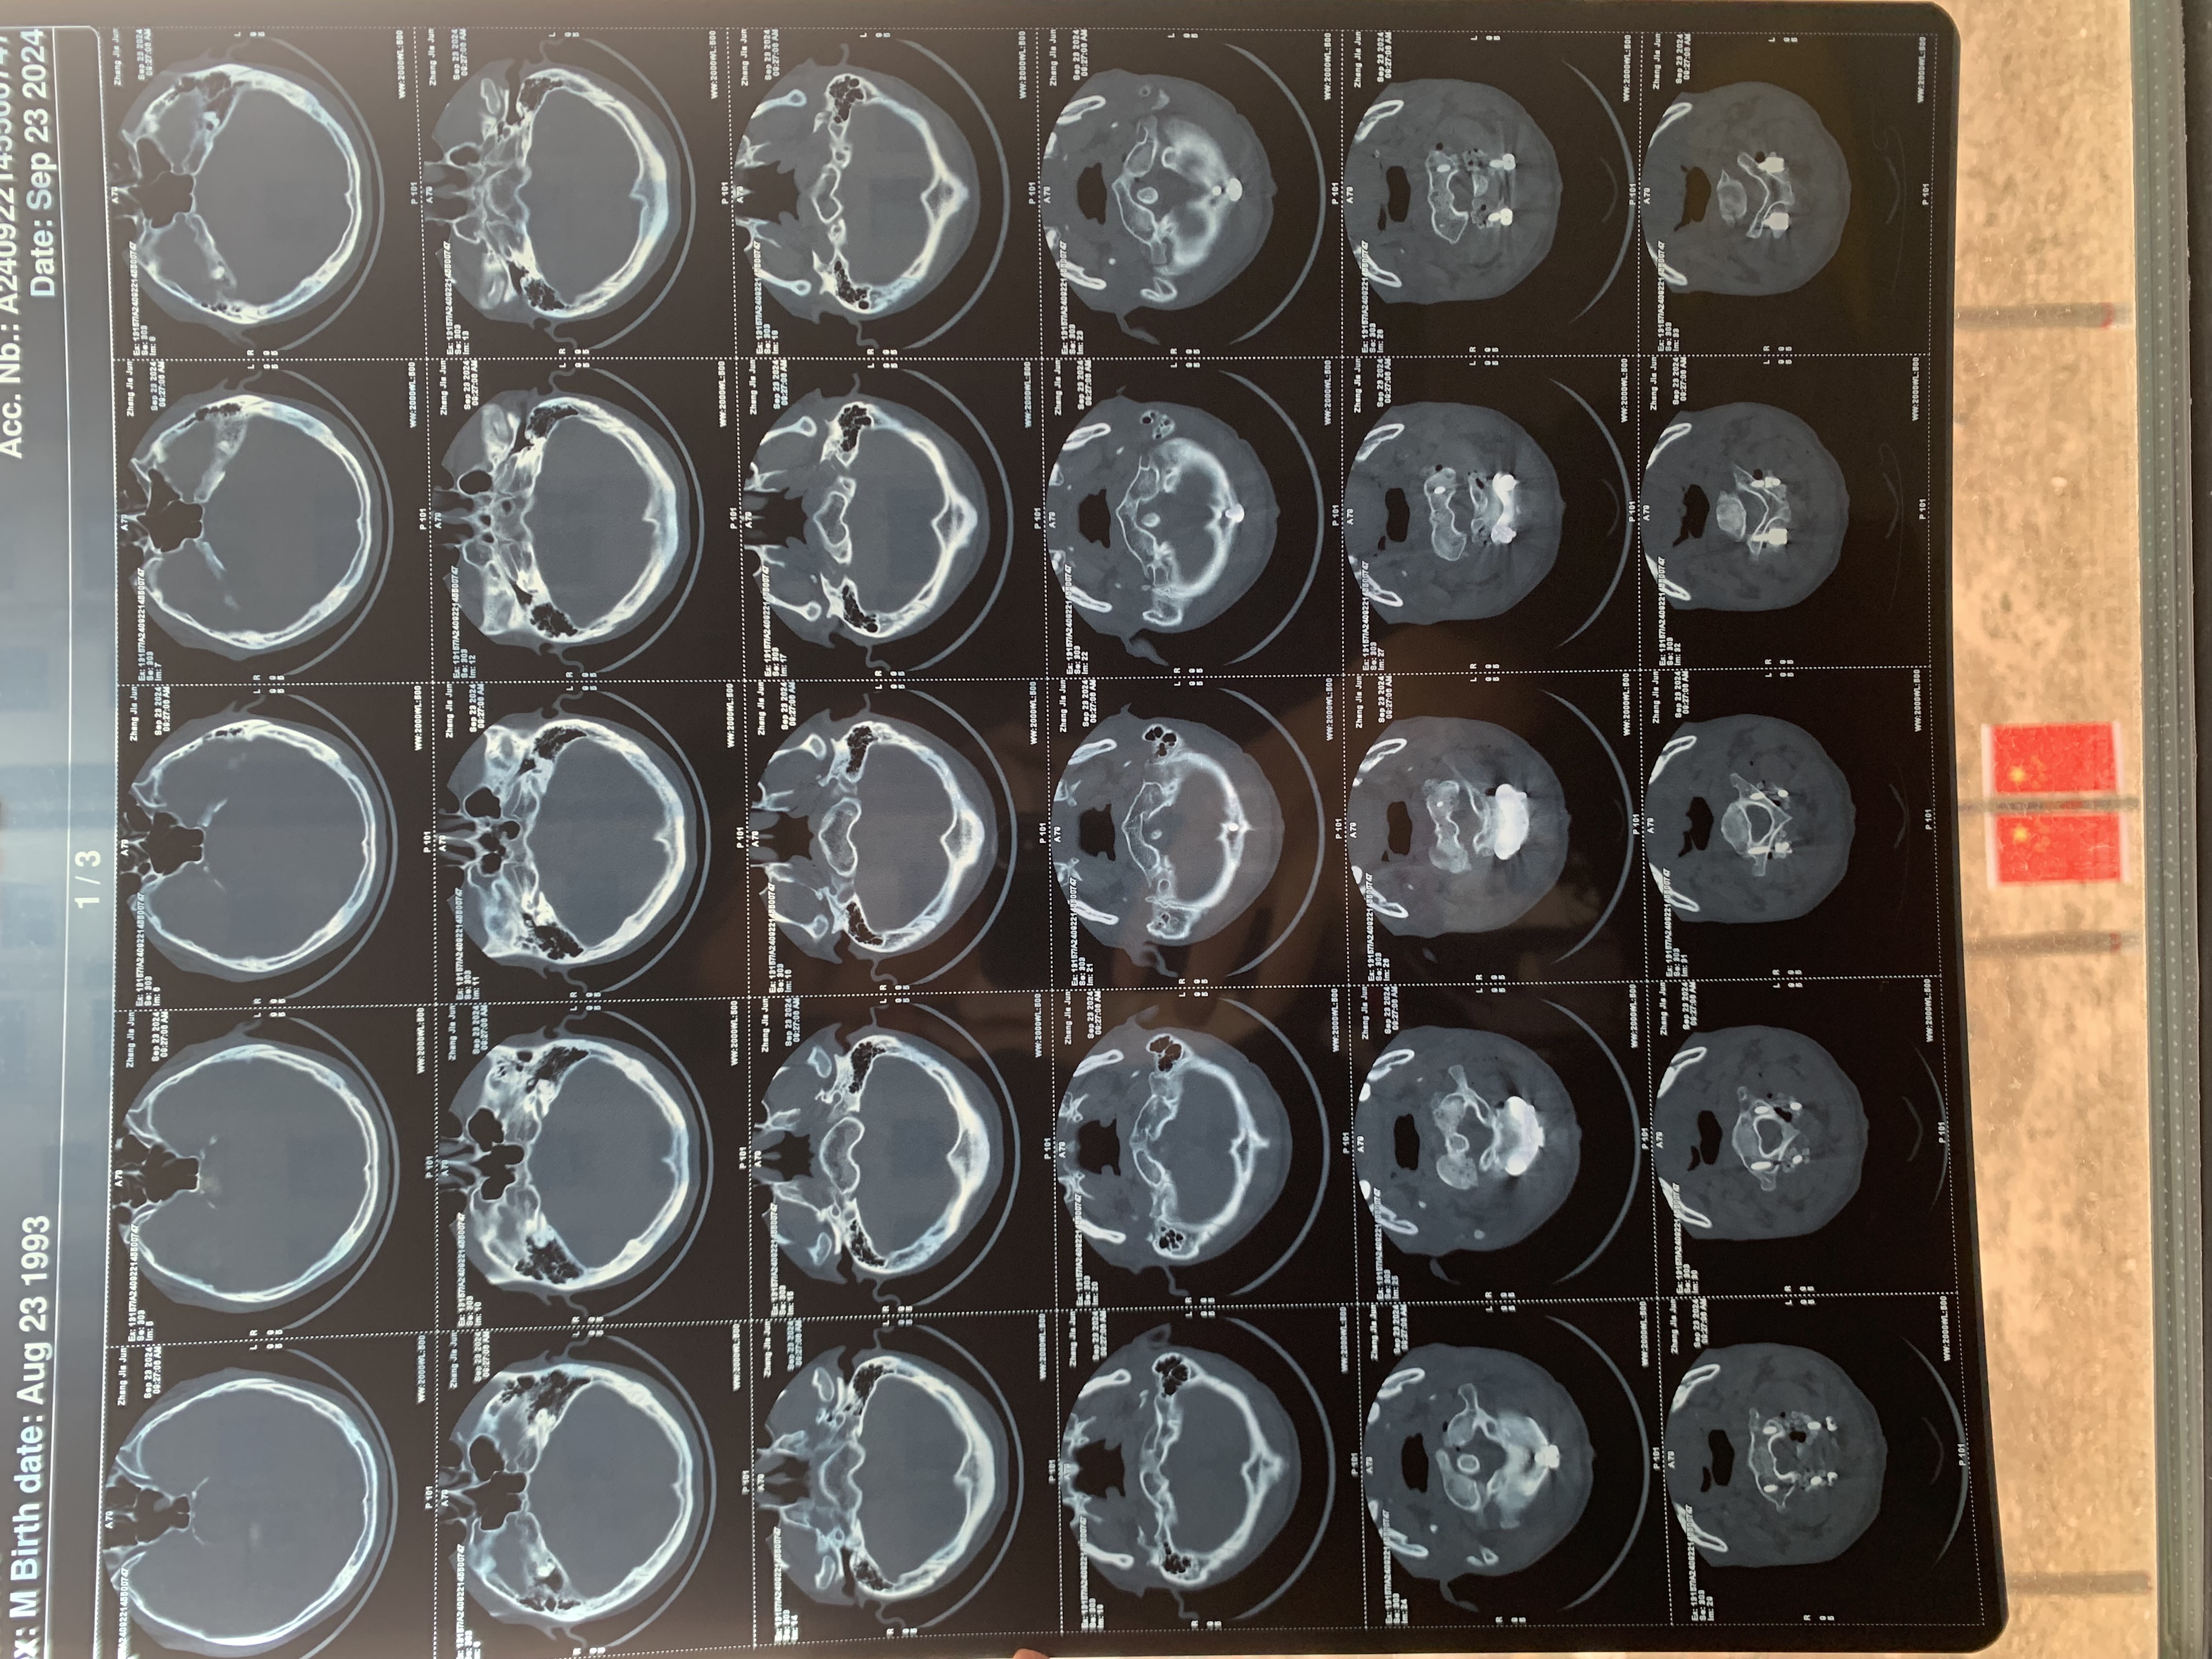

• 诊断:寰枢椎脱位、颅底凹陷

• 影像: